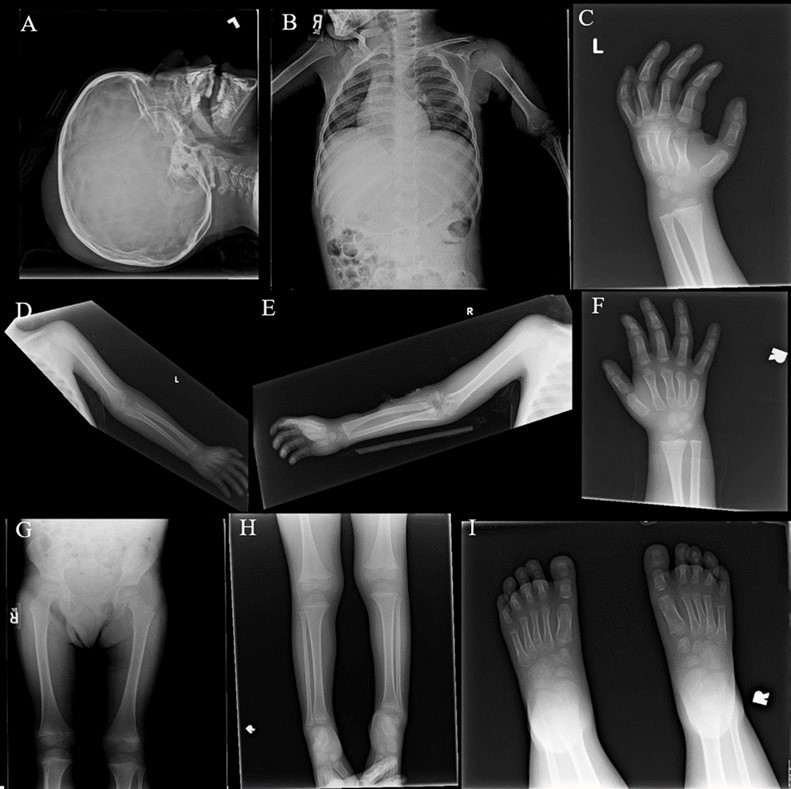

In developed nations, scurvy is an incredibly rare condition due to the availability of nutrient rich foods to most inhabitants. In the United States, only about 7% of the population is estimated to have a Vitamin C deficiency.1 Vitamin C deficiency does not necessarily equate to the development of scurvy, however. Symptoms of scurvy typically only present when plasma Vitamin C concentrations reach a level of 0.2 mg/dL.2 Although bone pain is a classic presentation of scurvy, if the patient presents early enough, imaging such as skeletal surveys and MRIs can be normal (Figure 2B - 2I) which often leads practitioners astray.3 Generally, scurvy is observed in populations of lower socioeconomic status, the elderly, and alcoholics.4 Given the low rates of scurvy across the United States and the fact that our patient did not belong to any classic high-risk groups, this case is particularly unusual.

From a musculoskeletal standpoint, MRIs of the cervical, thoracic, and lumbar spine were within normal limits. The patient was started on scheduled acetaminophen for pain management. A CT of the head without contrast showed right high convexity scalp soft tissue swelling without acute intracranial abnormality (Figure 1A – 1F). A complete bone survey was negative for sources of trauma (Figure 2B – 2I) but did note calvarial soft tissue edema (Figure 2A). A head ultrasound confirmed the fluctuance on the patient’s skull to be a subgaleal hemorrhage (Figure 3A – 3C) of 9 mm thickness at its greatest.

Figure 2A - 2J.X-Ray complete bone survey. 2A: Lateral view of the skull, 2V. 2B: Frontal view of chest, abdomen and pelvis (spine), 1V. 2C: Frontal view of left humerus, 2V. 2D: Frontal view of left hand, 2V. 2E: Frontal view of right humerus, 2V. 2F: Frontal view of right hand, 2V. 2G: Frontal view of both femora, 1V. 2H: Frontal views of both lower legs, 2V. 2I: Frontal views of both feet, 2V. Findings include calvarial soft tissue edema. No additional injury detected on these radiographs.

X-Ray complete bone survey. 2A: Lateral view of the skull, 2V. 2B: Frontal view of chest, abdomen and pelvis (spine), 1V. 2C: Frontal view of left humerus, 2V. 2D: Frontal view of left hand, 2V. 2E: Frontal view of right humerus, 2V. 2F: Frontal view of right hand, 2V. 2G: Frontal view of both femora, 1V. 2H: Frontal views of both lower legs, 2V. 2I: Frontal views of both feet, 2V. Findings include calvarial soft tissue edema. No additional injury detected on these radiographs.